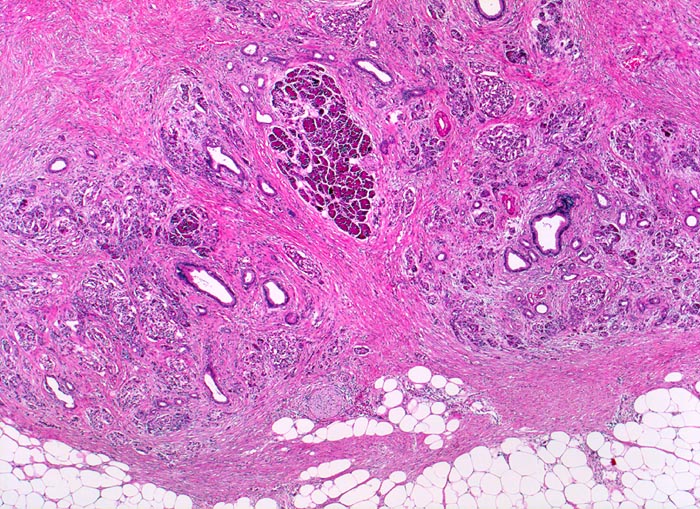

Die Nekrosen des interlobulären Gewebes und der interlobulären Gänge bei ethylischen Pankreatitisschüben führen primär zu einer interlobulären Fibrose und interlobulären Gangstrikturen. In den betroffenen interlobulären Gängen führt der Sekretstau zur Konkrementbildung (verkalkte Proteinpräzipitate). Wie bei einer chronisch obstruktiven Pankreatitis kommt es in den unvollständig drainierten Läppchen zu einer Atrophie der Azini verbunden mit intralobulärer Fibrose. Letztere Areale enthalten schliesslich nur noch Reste unregelmässig verteilter Gänge, Inseln, Nerven und Gefässe. In vielen Fällen lassen sich extrapankreatische Pseudozysten gefüllt mit nekrotisch-hämorrhagischem Detritus in der Nachbarschaft der fibrosierten Bezirke nachweisen.

Ein Tumor ( 2066), eine Narbe oder einen Stein können als Folge einer Obstruktion des Pankreasganges im Pankreaskopf eine diffuse Atrophie und Fibrose des Pankreas nach sich ziehen. Diese Form wird als chronische obstruktive Pankreatitis bezeichnet und ist gekennzeichnet durch eine deutliche poststenotische Dilatation des betroffenen Pankreasganges ohne Konkrementbildung und eine diffuse Fibrose des an den obstruierten Gang angrenzenden Parenchyms.

Breite Bänder von sklerosiertem zellarmem Bindegewebe verlaufen zwischen den Läppchen.

Atrophie des exokrinen Pankreas.

Erhaltene Inseln und Gangstrukturen.

Spärliches chronisches Entzündungsinfiltrat.